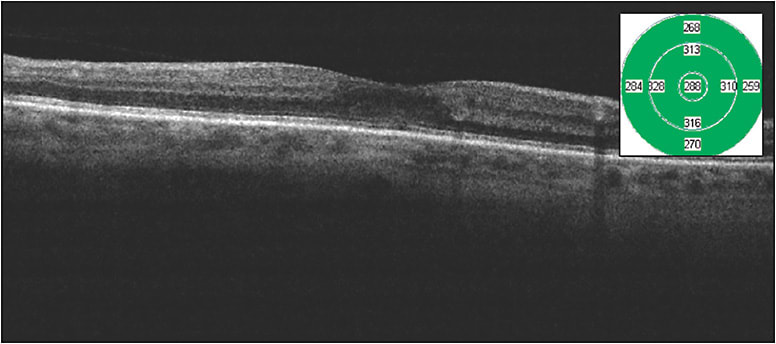

Figures 1 and 2 show images of a patient with moderate nonproliferative diabetic retinopathy and foveal-involving macular edema with excellent vision. It is difficult in my treatment discussions to march down the anti-VEGF path for these patients, because they are asymptomatic and often in the workforce, and I am unable to provide them an accurate prediction of the number of injections needed to achieve anatomic success. This patient received a single micropulse laser treatment and improved from a CFT of 318 µm to 288 µm with a visual acuity improvement from Snellen 20/30 to 20/25 over 2 months. This is a very good outcome for patients such as this.